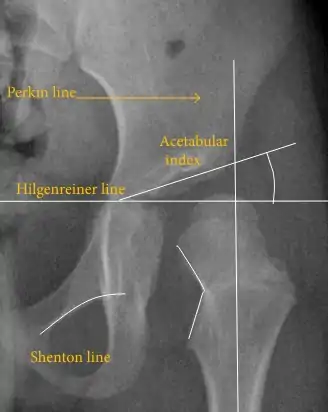

Hip dysplasia can be diagnosed by ultrasound[42] and projectional radiography ("X-ray").[43] Ultrasound imaging is generally preferred at up to 4 months due to limited ossification of the femoral head up until then, and is the most accurate method for imaging of the hip during the first few months after birth. However, in most instances, ultrasound screening should not be performed before 3 to 4 weeks of age because of the normal physiologic laxity.[44][notes 1] When universal with targeted ultrasound screening was compared, the former results in an insignificant reduction in the late diagnosis of hip dysplasia, which is why universal ultrasonographic screening of newborn infants is not recommended by the American Academy of Pediatrics.[11]

Despite the widespread use of ultrasound, pelvis X-ray is still frequently used to diagnose or monitor hip dysplasia or for assessing other congenital conditions or bone tumors.[45]

The most useful lines and angles that can be drawn in the pediatric pelvis assessing hip dysplasia are as follows:[45] Different measurements are used in adults.[45]